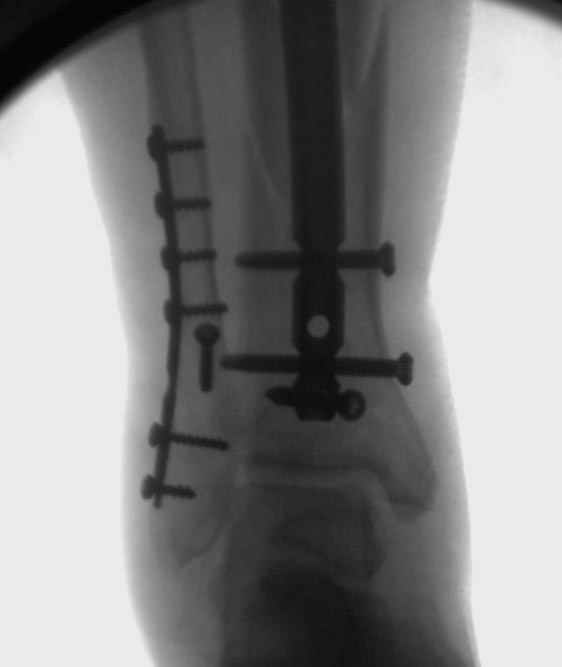

Здесь мы использовали новый Synthes Nail с дополнительными дырками, в проксимальной части 4: по две косых и поперечные (один стандартный а другой динамический), в дистальной части две поперечные, прямая и косая. Вес больного более 120 кг, нагрузку начнем через месяц.